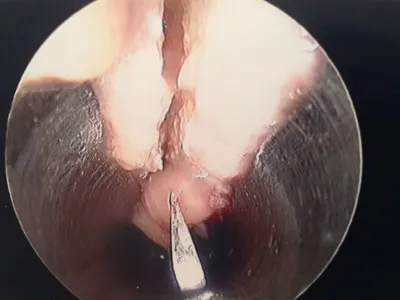

More Intraop Pics of Endoscopic Plantar Fascia Release. The thickened fascia is seen on the left. The Blade is cutting through the fascia in the center pic and confirmation of complete release of that portion of the ligament is noted as we can see the intrinsic muscles after release.